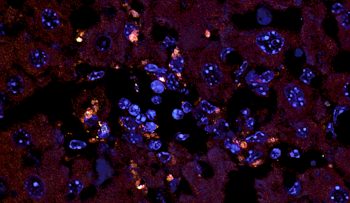

Cercetătorii de la prestigioasa universitate americană au testat această teorie pe Enterococcus gallinarum, o bacterie ce poate „călători” în afara intestinului și poate ajunge la ganglionii limfatici, ficat și splină. În imaginea de mai sus, porțiunile de culoare oranj reprezintă bacteria Enterococcus gallinarum ajunsă în țesuturile ficatului. Studii anterioare au arătat faptul că bacteriile intestinale au legătură cu afecțiunile autoimune, în care sistemul imunitar atacă țesuturile sănătoase. Noul tratament a reușit cu succes să suprime dezvoltarea bacteriilor și să oprească efectul acestora asupra sistemului imunitar.